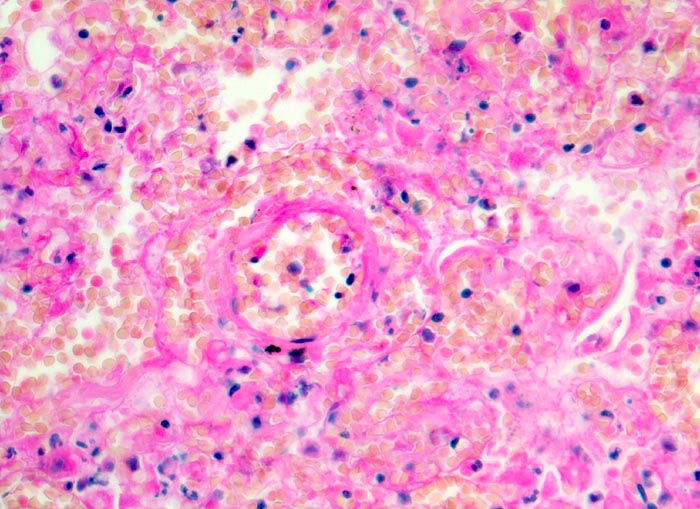

hämorrhagischer Lungeninfarkt

vaskulär / Durchblutungsstörung

Lunge

Das Lungengerüst ist nur noch schattenhaft erkennbar. Die Kerne der nekrotischen Zellen sind stark abgeblasst. Das nekrotische Parenchym ist blutig durchtränkt.

Tiefe Beinvenenthrombosen bei metastasierendem Prostatakarzinom. Koronare Herzkrankheit.

Histologie

320